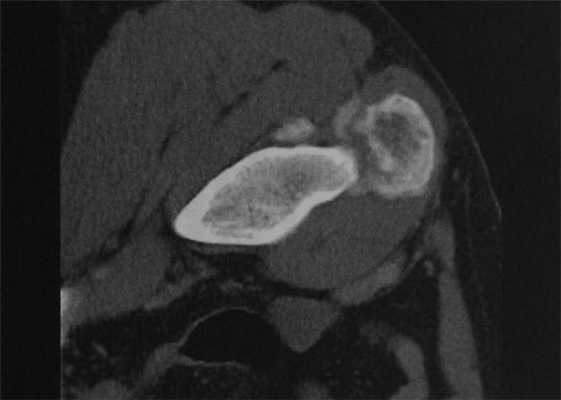

Мужчина 32 лет. КТ. Травматическое повреждение правой паховой области за несколько лет до исследования. В месте прикрепления прямой мышцы живота округлый зрелый участок окостенения с периферическим формированием нового кортикального слоя, типичный для оссифицирующего миозита. В отличие от околокостной остеосаркомы, при оссифицирующем миозите кальцинаты крупнее на периферии, чем в центре.